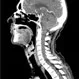

Brain Cancer: Tumor Signs, Symptoms, and TreatmentBrain cancer, types of which include primary or secondary cancer, involves invasive brain tumors including gliomas and glioblastomas. Learn the brain cancer survival rate, treatment options including chemotherapy, and the different brain tumor grades. Find out how the right treatment plan can fight cancerous brain tissue.